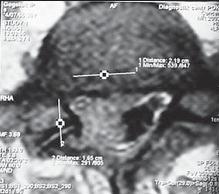

На МРТ № 18 наблюдаются грыжи межпозвонковых дисков в сегментах: — LIV-LV вентральной локализации с образованием каудального секвестра; при расположении межпозвонковой грыжи на один сегмент выше, «конфликт» с брюшной аортой был бы неизбежен; — LV-SI — дорсальная грыжа межпозвонкового диска, частично компенсированная спондилёзом МРТ № 19 ![]() МРТ № 20 ![]() На МРТ № 19 наблюдается дорсальная грыжа межпозвонкового диска шейного отдела позвоночника в сегменте СV-СVI с компрессией спинного мозга На МРТ № 20 наблюдается грыжа межпозвонкового диска шейного отдела позвоночника в сегменте CV—CVI и протрузия в сегменте CVI-CVII Замечу, что если грыжа межпозвонкового диска имеет достаточно большой размер и локализована в шейном отделе, то она способна вызвать не только соматические нарушения, но и даже психические расстройства. Причина кроется в сдавлении дурального мешка грыжей межпозвонкового диска (дуральный мешок — это герметичный соединительнотканный мешок, формируемый твёрдой мозговой оболочкой, в котором расположен спинной мозг). Как известно, спинной мозг не имеет болевых рецепторов. Однако вышеуказанная патология приводит к локальному устойчивому возбуждению определённых зон коры головного мозга. На субъективном уровне это может проявляться как постоянное чувство тревоги (так называемый «синдром ожидания»). Грыжи межпозвонковых дисков в грудном отделе позвоночника явление довольно редкое, но всё же наиболее опасное. Опасное потому, что эпидуральное пространство в грудном отделе позвоночника узкое по сравнению с другими отделами, в пределах всего 0,2–0,4 см по всей окружности дурального мешка (твёрдой оболочки спинного мозга). Поэтому даже небольшое грыжевое выпячивание может сдавить спинной мозг и вызвать тяжелейшие осложнения. Но, как уже говорилось, это явление в грудном отделе позвоночника редкое, поскольку высота межпозвонковых дисков довольно мала, всего около 3–5 мм, да и грудной отдел позвоночника менее подвижен по сравнению с другими отделами за счёт жёсткого рёберного каркаса, а значит, менее подвержен травматизации. МРТ № 21